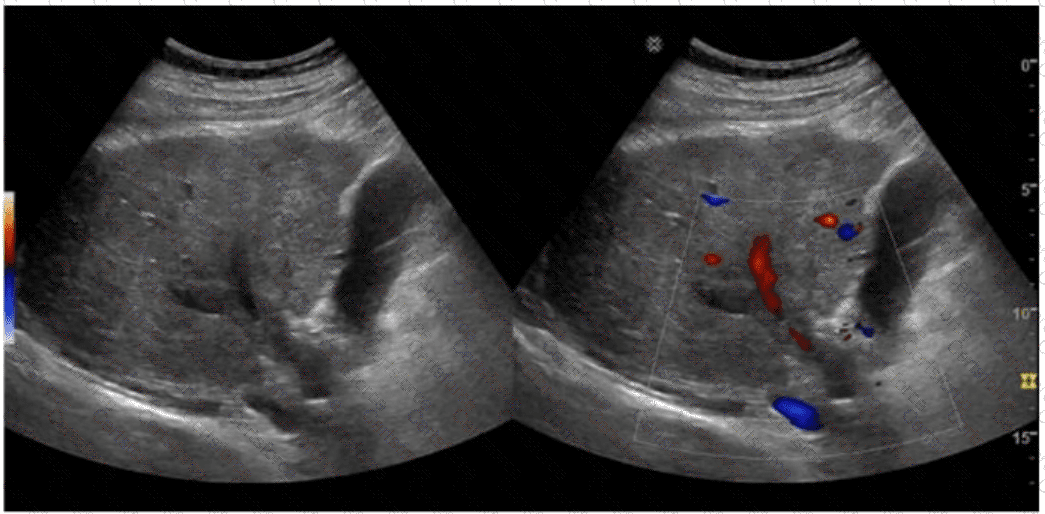

The sonographic images depict an acute thrombotic process involving the portal venous system. The absence of cavernous transformation in the setting of portal vein thrombus indicates that the process is acute. In chronic portal vein thrombosis, collateral vessels form in the porta hepatis to bypass the obstruction, a process known as cavernous transformation.

Echogenic thrombus within the portal vein lumen

Absence of flow on color Doppler

No evidence of cavernous transformation (i.e., no serpiginous collateral vessels at porta hepatis)

Cavernous transformation is a hallmark of chronic portal vein thrombosis and takes weeks to months to develop. Therefore, its absence on ultrasound supports an acute diagnosis.